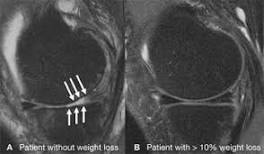

Weight loss can preserve knee cartilage in obese people The researchers investigated the link between different amounts of weight loss and the progression of knee cartilage degeneration - as shown on ...